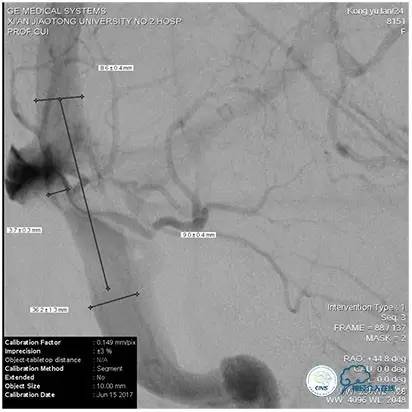

术中造影

5ml/s,总量8ml,压力100~150

手术方案

1、6mm×20mmAviator球囊(Cordis)分段对狭窄部位进行扩张。

2、植入7mm×40mmPrecise自膨支架。